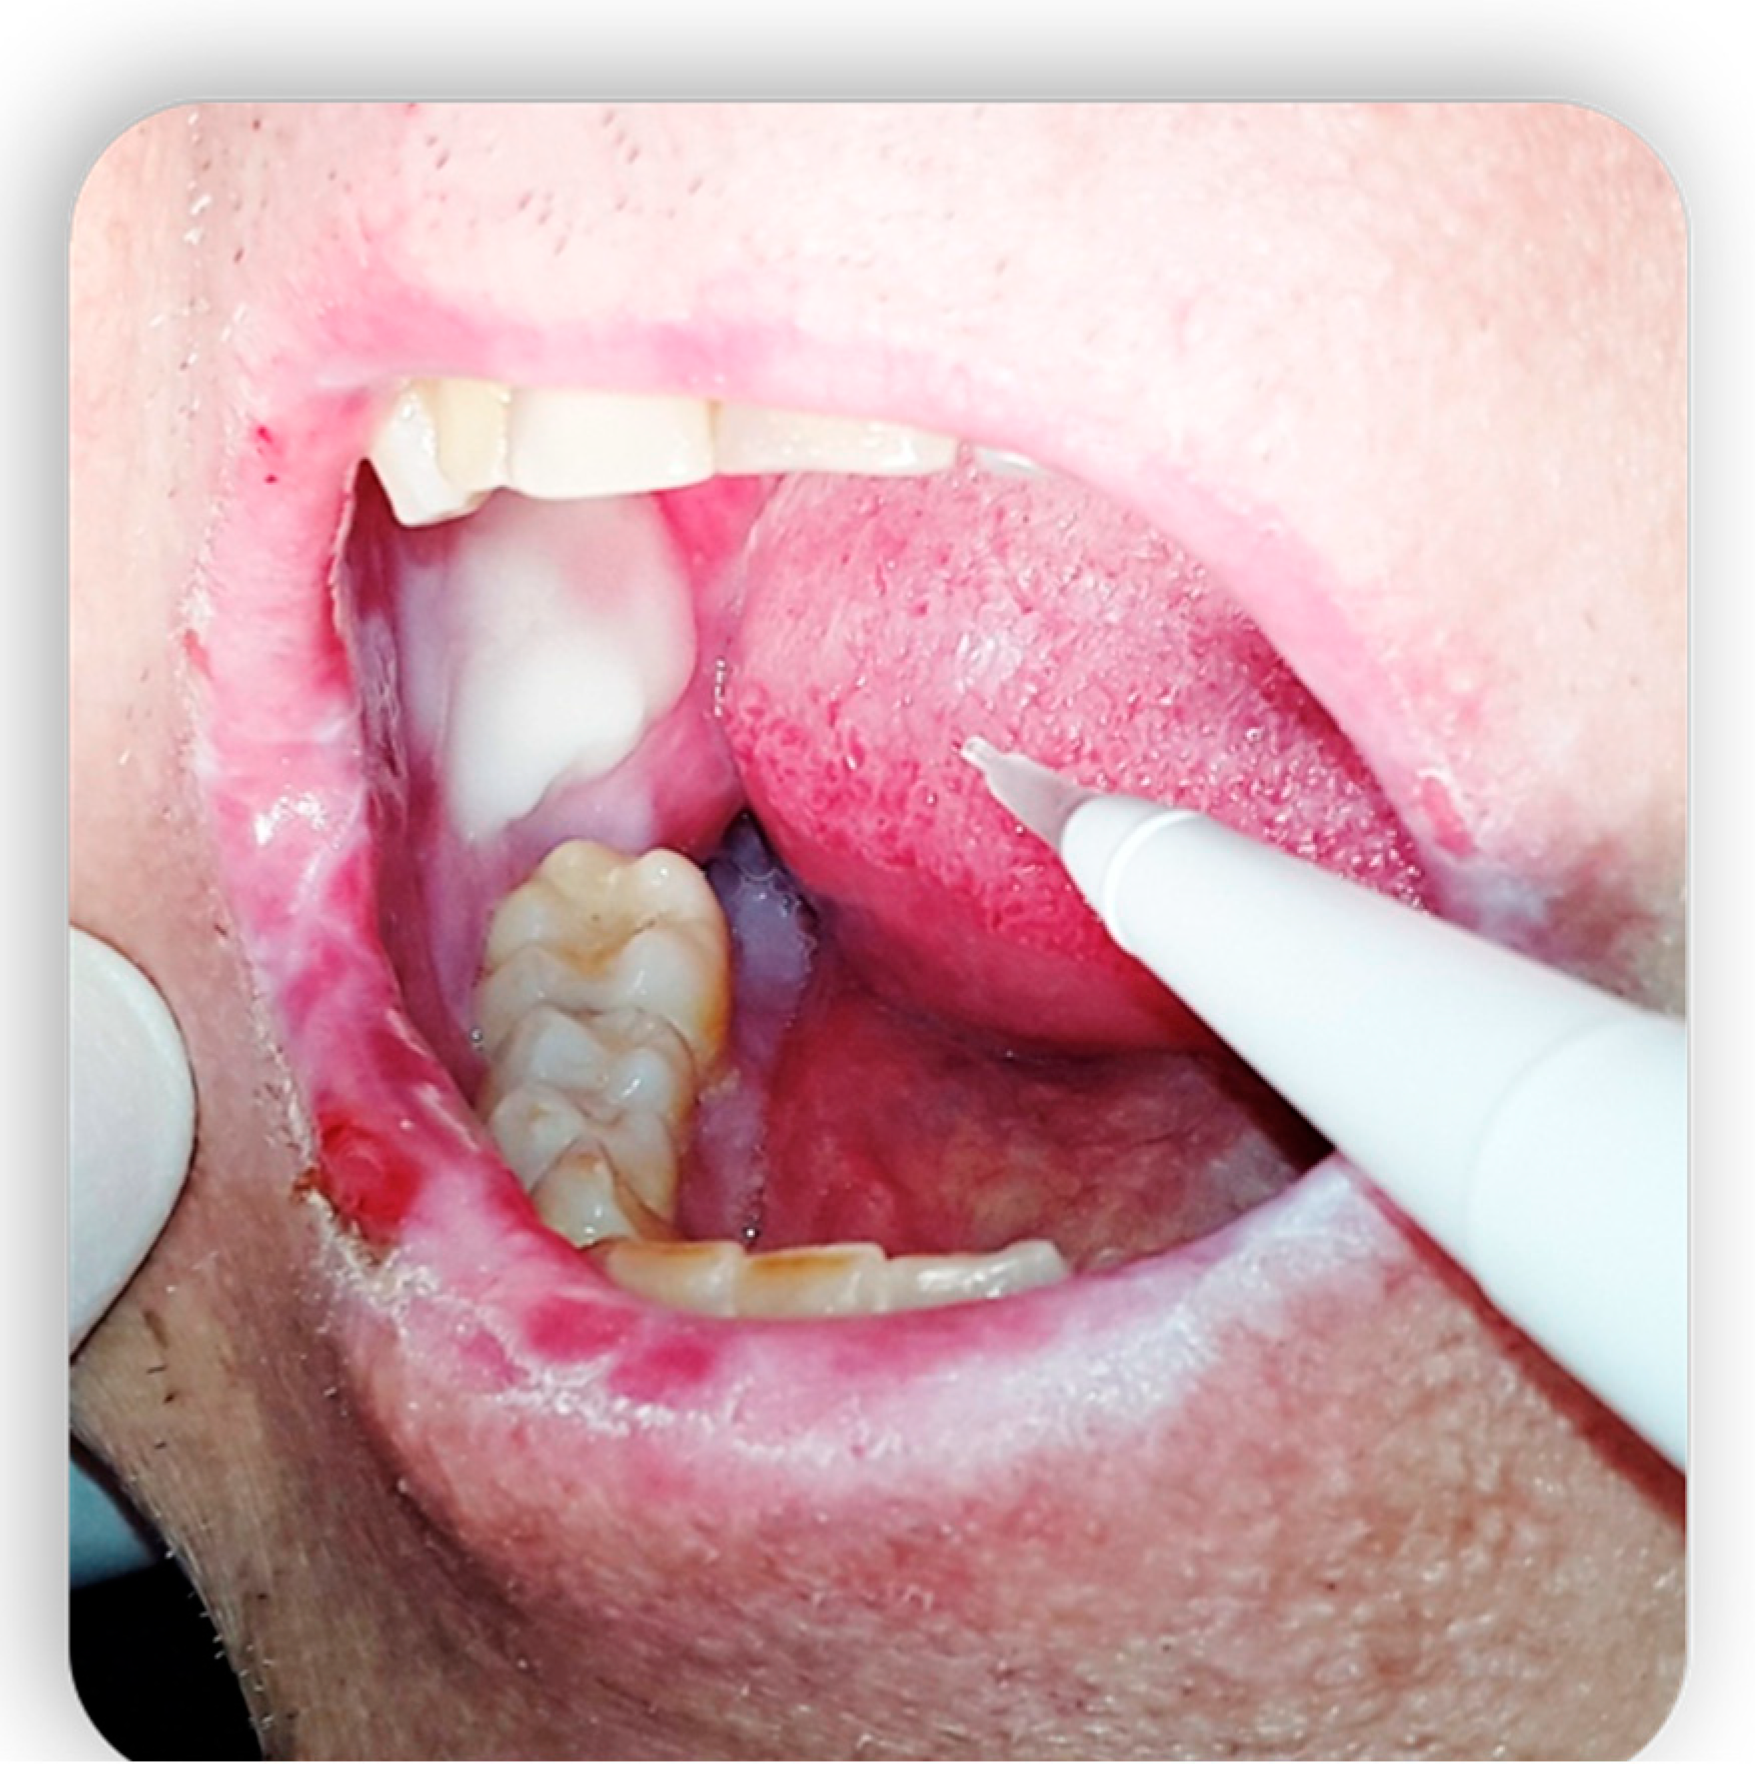

1.4.3. Oral cGvHD Manifestation

Chronic GvHD is the main cause of functional impairment of the oral cavity in patients suffering from GvHD. The oral cavity appears to be the second most frequently involved site in the chronic form in PBSC transplants with a frequency of about 90% (second only to the skin) [34]. The oral cavity is the first involved area in BM transplants (Figure 5 and Figure 6), with a frequency of about 80% [35].

Figure 5.

Oral cGvHD manifestation: Labial commissure ulcerations that reduce mouth opening.

Figure 6.